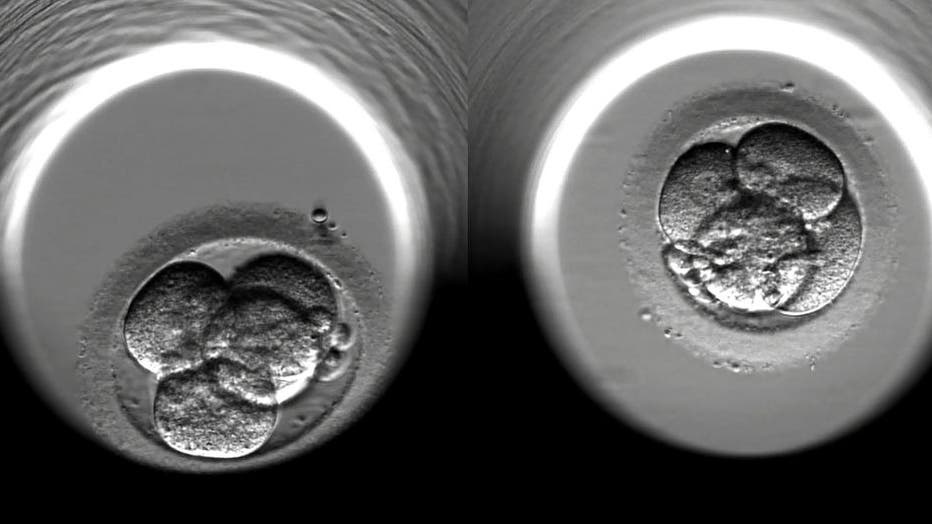

LONDON - 2016: This undated screen grab shows the cell-division of two fertilized human embryos during the first 48 hours of embryonic development following IVF treatment at a private clinic in London. The medical world is marking the 40th Anniversar